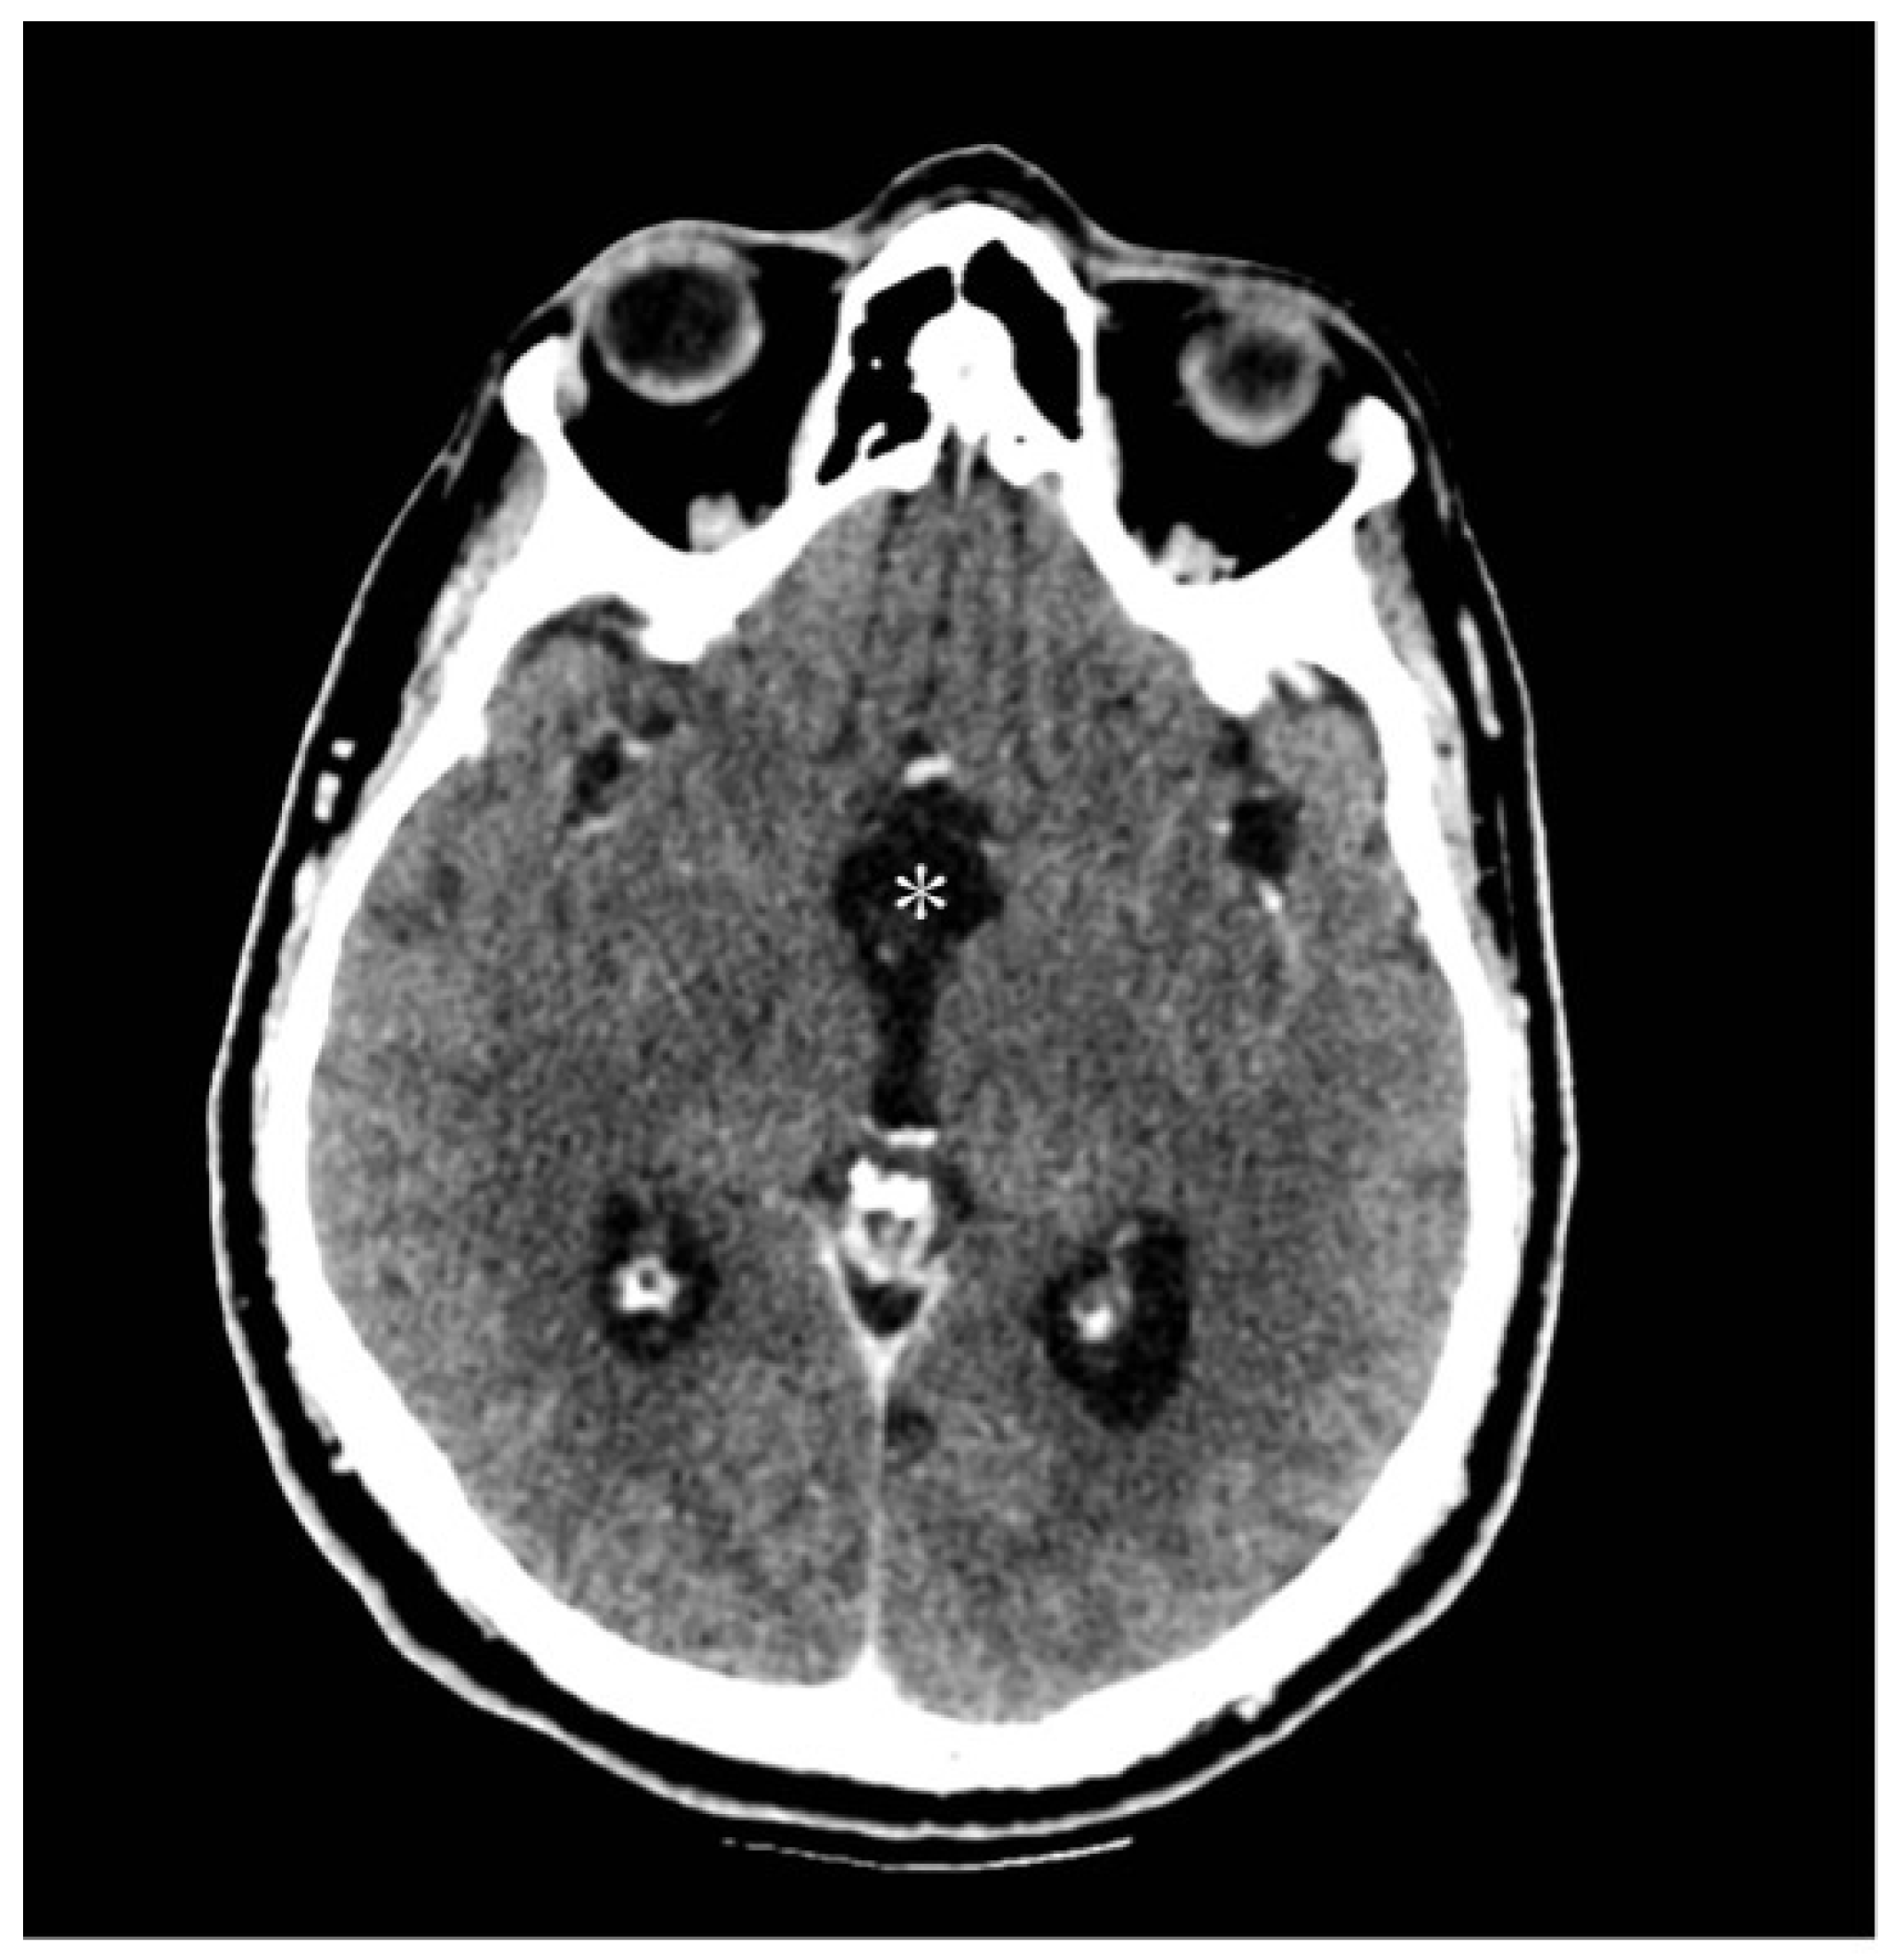

3.2.2. Radiological Findings

| Present case | / | 48 | Male | Third nerve palsy, stuporous state | Gross total | SWI_sequences with intralesional bleeding, microcalcification. Post-contrast administration revealed intense enhancement and increased perfusion indexes | Transient DI, hypopituitarism | 1 year | Transcranial |